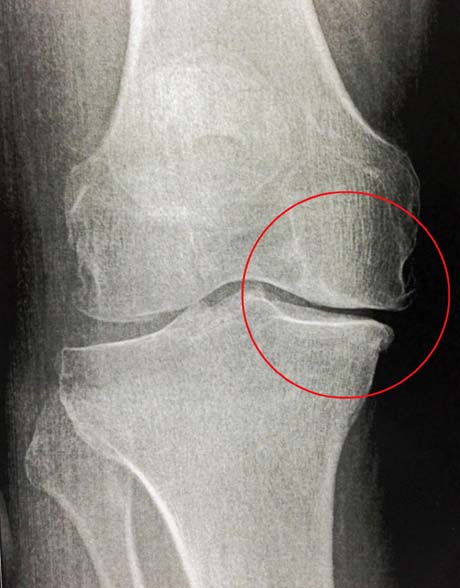

Ο ακτινολογικός έλεγχος των γονάτων αναδεικνύει το πρόβλημα της αρθρίτιδας στο έσω διαμέρισμα του γόνατος. Η αξιολόγηση του μηχανικού άξονα των κάτω άκρων θεωρείται απαραίτητη.

Αρθρίτιδα στο έσω διαμέρισμα των γονάτων (βέλη)

Η μαγνητική τομογραφία αναδεικνύει τη βλάβη του αρθρικού χόνδρου καθώς και την κατάσταση των μηνίσκων και των μαλακών μορίων